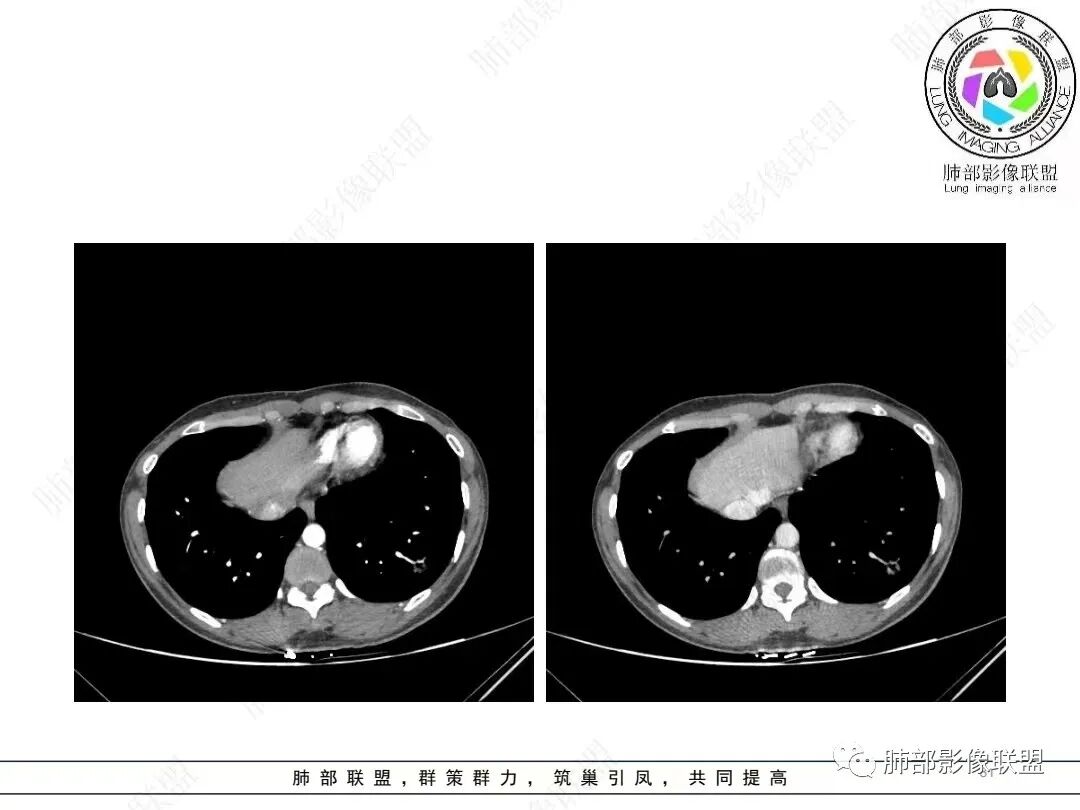

肺动脉供血

@张明辉临沂市人民医院 今天病例粗大肺动脉供血+空洞结节,和我上传病例比较像。

肺动脉为主征的话,PSP要考虑,还有贴边的意思

唐老师说的有道理,常规进入肿瘤的血管不会这么粗,PSP确实要考虑。